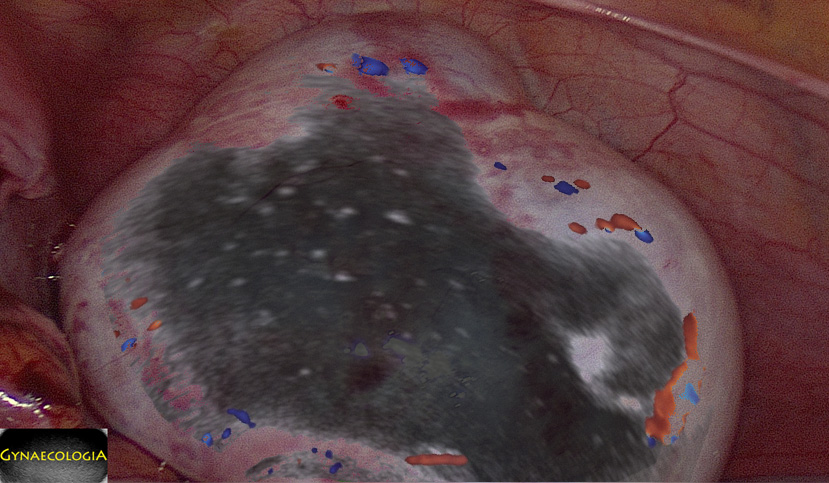

Emergency laparoscopy.

To preserve the ovary, surgical management should not be delayed (onset of symptoms – surgery < 24 hours, ideally < 6 hours).

It is of major importance that visual assessment of ovarian necrosis during surgery does not seem to be a good predictor of actual necrosis in histopathology.